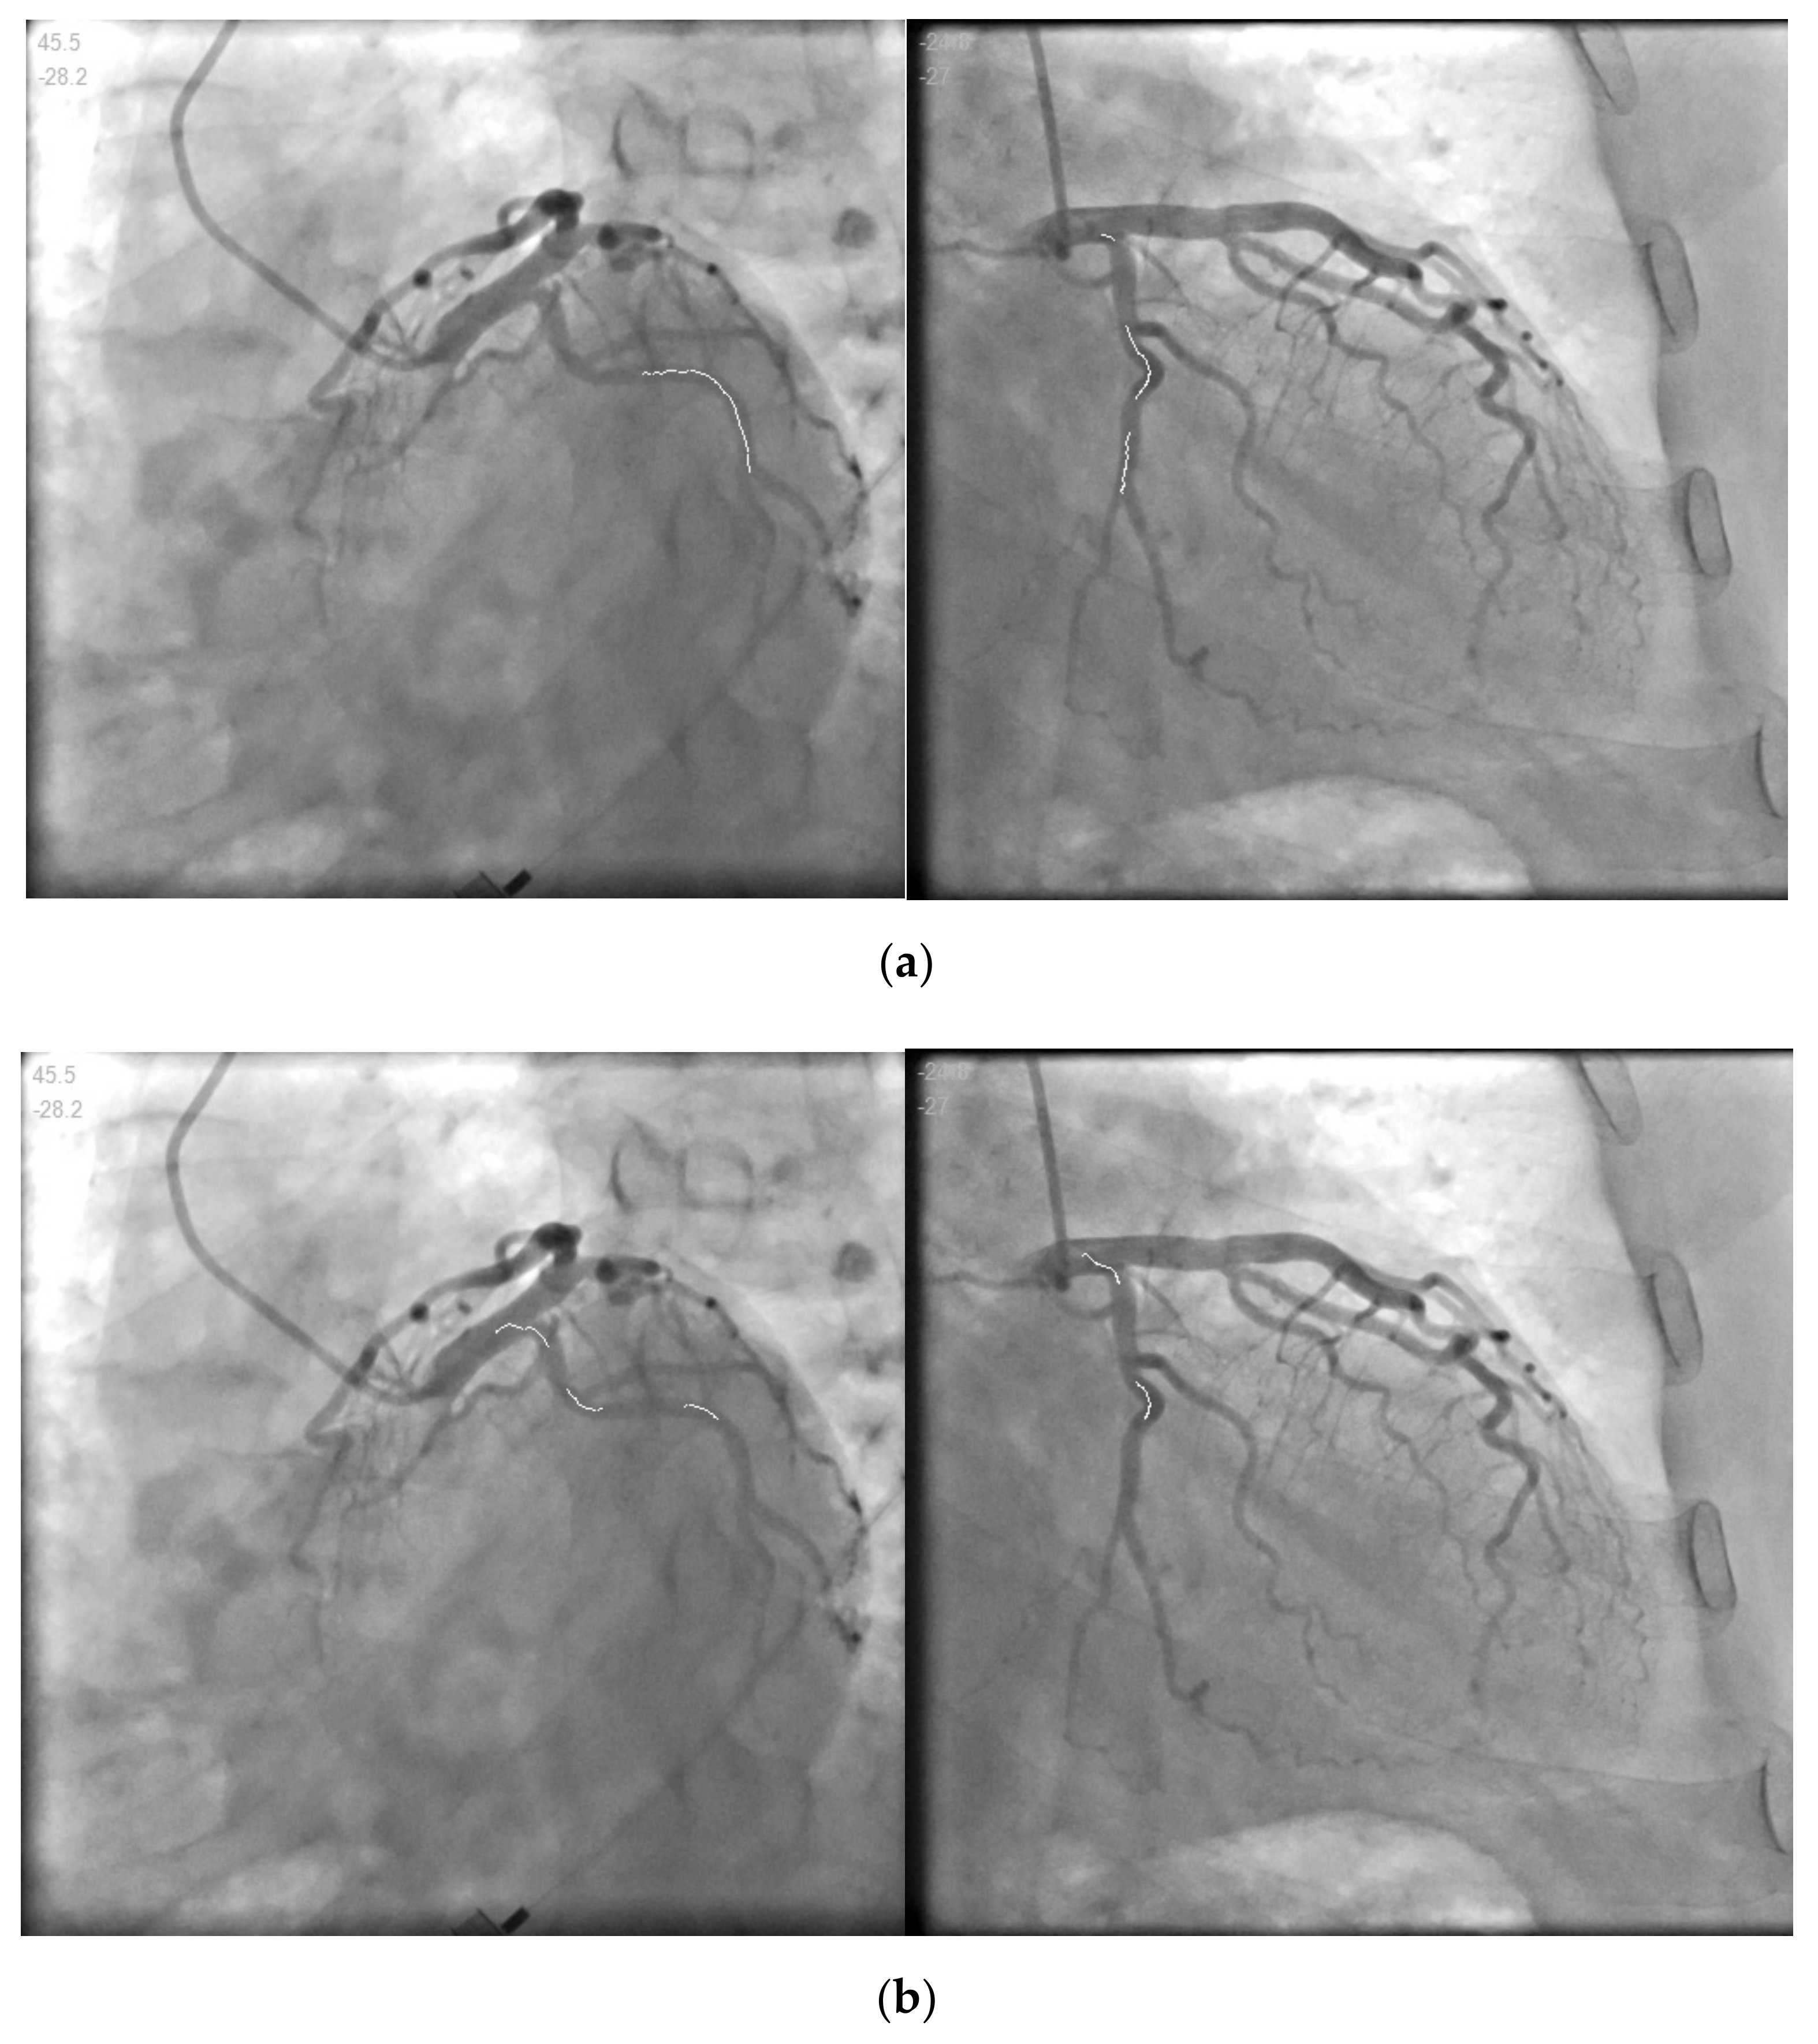

| Data.1 | (a) | 45.5 | −28.2 | 1200 | 749 |

| (b) | −24.8 | −27 | 1147 | 844 | |

| Data.1 | (a) | Match 1 | 1.90582 | 0.00175 | 0.79173 | 0.49422 | 83.1266 |

| Match 2 | 0.70741 | 0.00123 | 0.13104 | 0.1651 | 4.2336 | ||

| Match 3 | 0.6653 | 0.06917 | 0.12584 | 1.99264 | |||

| (b) | Match 1 | 1.74575 | 0.0016 | 0.73019 | 0.4522 | / | |

| Match 2 | 0.66112 | 0.00116 | 0.12136 | 0.1535 | / | ||

| Match 3 | 0.62295 | 0.06439 | 0.11788 | / | |||